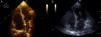

Caso clínico 3Uma mulher de 47 anos, obesa e com insuficiência venosa periférica, foi admitida no serviço de urgência por síncope, dispneia de início súbito, dor epigástrica, insuficiência respiratória grave e choque. Tinha iniciado toma de anticoncecional oral três dias antes da admissão. Poucos minutos após a admissão verificou‐se PCR em ritmo de atividade elétrica sem pulso (AESP), tendo sido iniciado SAV. Verificaram‐se vários episódios de recuperação de circulação espontânea seguida imediatamente de nova PCR. O ecocardiograma TT revelava dilatação das câmaras direitas (Figura 3A), IT grau III/IV (PSAP 45mmHg+PVC), fluxo pulmonar compatível com HTP e depressão da função sistólica do VD.

Por suspeita de choque obstrutivo por TEP de alto risco, realizou trombólise endovenosa com bólus de 50mg alteplase, com recuperação definitiva de circulação espontânea após cerca de 45 minutos de SAV. O angioTAC torácico mostrou focos tromboembólicos na porção distal de ambas as artérias pulmonares, na emergência das várias artérias lobares e de forma mais expressiva nos ramos segmentares da artéria lobar inferior direita (Figura 2). Por manter o quadro de choque refratário a medidas de suporte foi submetida a TR com AngioJet®, verificando‐se melhoria hemodinâmica imediata e melhoria angiográfica parcial. A doente permaneceu com suporte ventilatório e aminérgico durante dez dias, tendo tido evolução clínica favorável desde então com recuperação neurológica total. O ecocardiograma realizado um mês após o evento não evidenciava dilatação ou disfunção ventricular direita nem sinais sugestivos de HTP (Figura 3B). Teve alta ao final de 37 dias de internamento hospitalar.